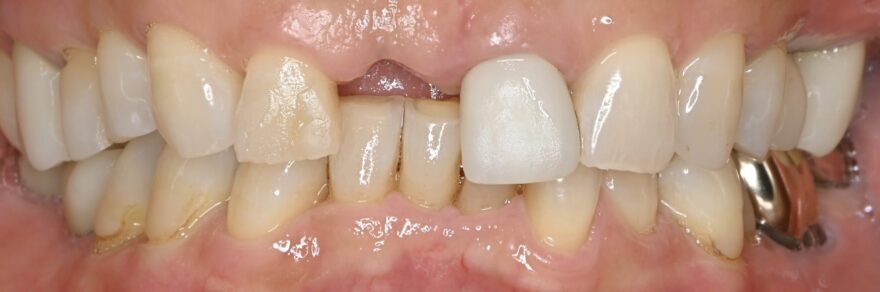

初診時口腔内写真

かかりつけの医院さんで、前歯のインプラント治療はできないと言われての、当院受診でした。

初診時レントゲン写真

このように、前歯の欠損部にブリッジもしくは入れ歯を他院さんで提案されてしまい、当院にご相談に来られる患者様が多数いらっしゃいます。